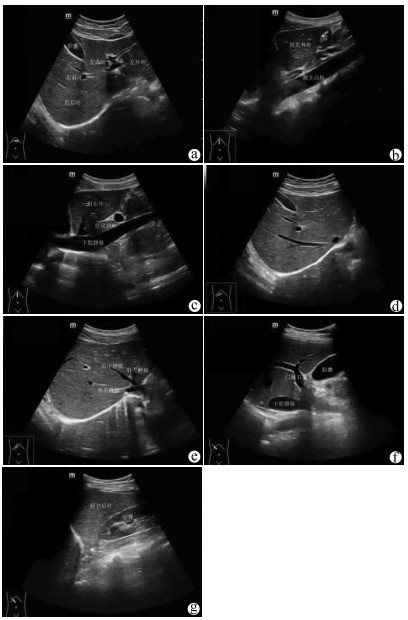

Influence of arterial variation and reconstruction of the donor hepatic artery in liver transplantation on early postoperative arterial complications

Bo HE, Xin WANG, Feng WANG, Yandong SUN, Qingguo XU, Ge GUAN, Yunjin ZANG

2021, 37(8): 1901-1904. DOI: 10.3969/j.issn.1001-5256.2021.08.030

Abstract(1199) HTML (300) PDF (2761KB)(185)

Abstract: